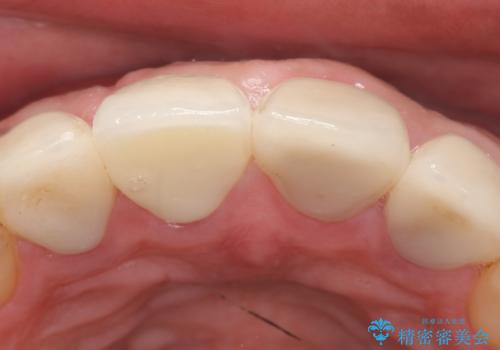

- 右上の前歯が土台ごと外れたといらっしゃった方の症例です。

ファイバーコアという土台から建て直し、咬み合わせに十分注意した上で、オールセラミッククラウンによる補綴を行いました

今回用いたオールセラミッククラウンはジルコニアフレームという白い素材の上にセラミックを盛っているため、審美性が非常に高いのが特徴です。